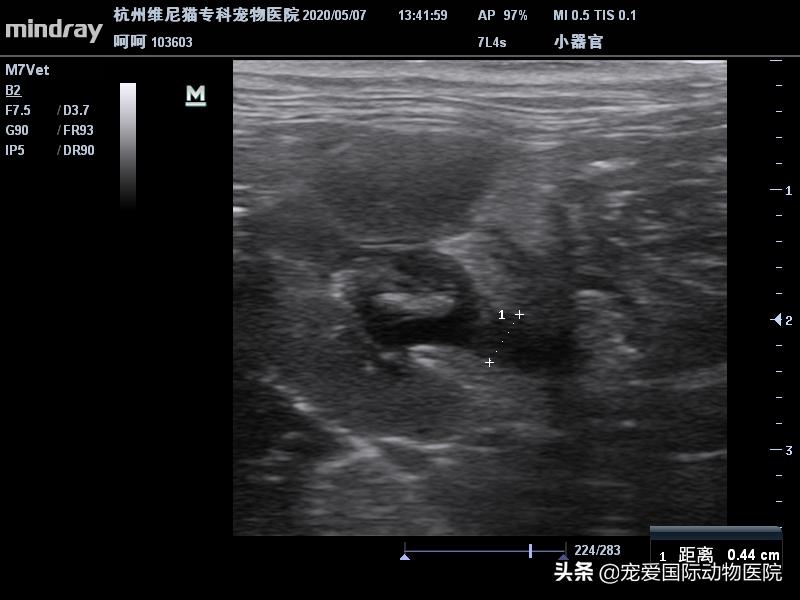

未见明显扩张输尿管,遂镇静造影

右侧肾结石,右侧输尿管堵塞

输尿管全程未探及明显结石

切开肾脏取出结石,经肾盂疏通